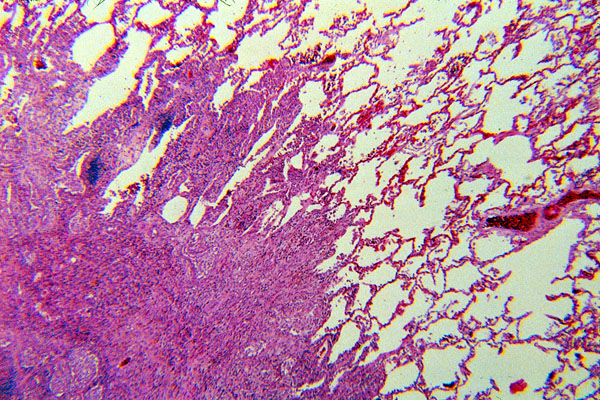

Pulmonary eosinophilic granuloma is a patchy, nodular interstitial lesion that often has an irregular or stellate outline owing to the extension of the interstitial infiltrate along the alveolar septa. The infiltrate may be cellular, or as healing progresses, the entire lesion may be transformed into a stellate scar. This slide shows partially healed lesions with some areas representing scars and other areas containing the cellular infiltrate of eosinophilic granuloma.